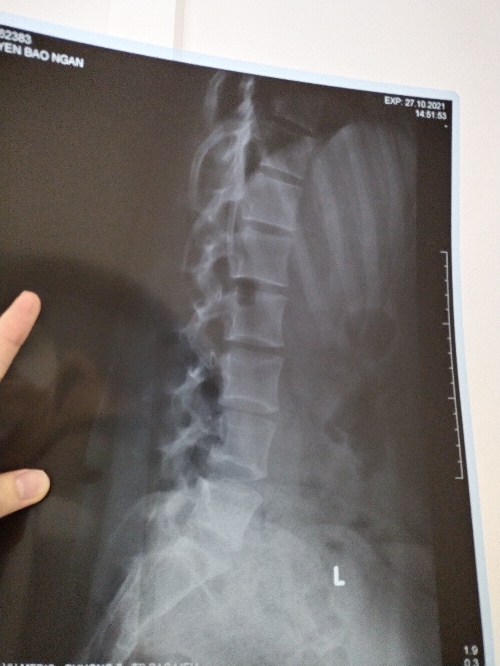

Thưa Bác Sĩ e hay bị đau xương mông với thắt lưng, e có đi chụp MRI mà bác sĩ xem kết quả nói e bình thường không bị sao rồi cho thuốc uống mà tới nay hơn tháng e vẫn còn bị đau ạ!